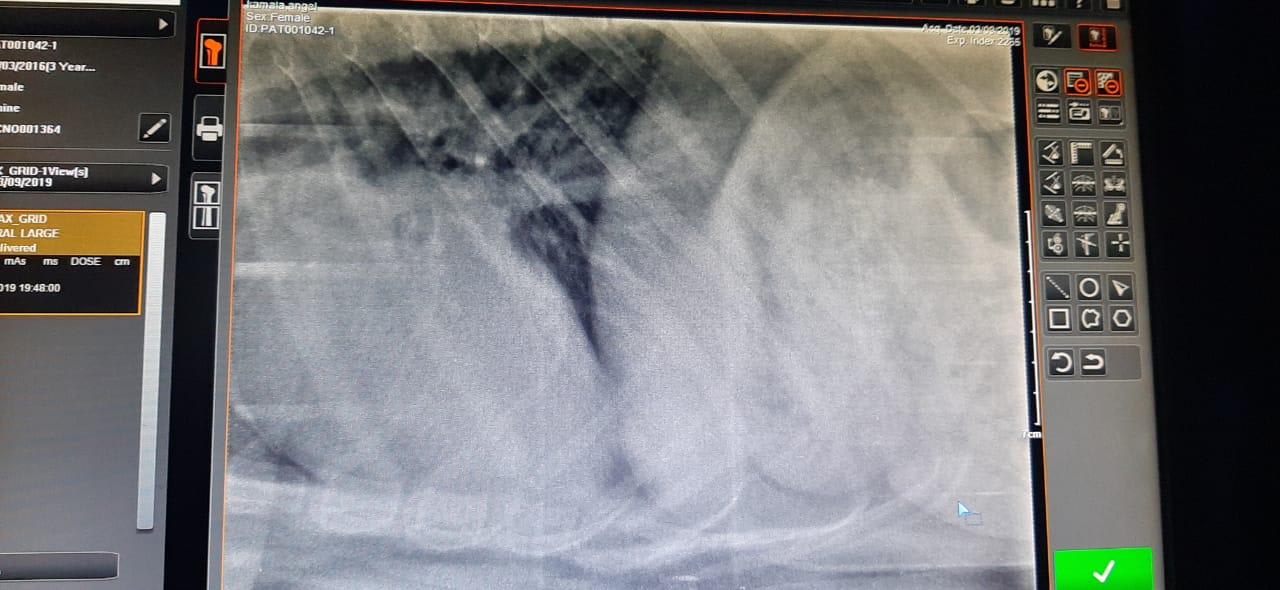

My pet had a seizure like thing yesterday. Today we had taken her to the vet. He did a heart x-ray. He said the VHS is 12.6. My pet was very nervous and scared when we were handling her during the X-ray. She was breathing very loudly and in speed because we were holding her legs and face. Is the high rate in VHS because of that? What is the estimated VHS for Labrador retrievers. Is it dangerous? Is the high rate in VHS because of her being nervous? I'm extremely worried and scared. Please help.

Hello, and thanks for your question on Petco Pet Education Center, formerly Petcoach. VHS or Vertebral Heart Score is a measure of the size of the heart, and would not be related to the dog's respiratory rate or level of anxiety. Normal VHS usually ranges from 8.5-10.5, so Angel's VHS is a bit high. There are a number of things that could cause a heart to become larger than normal, so to have more information about what might be causing the increased size of Angel's heart, an echocardiogram (ultrasound of the heart) should be performed. Your primary vet should be able to help guide you to a specialty vet clinic that would be able to perform an echo. Hope this helps, and good luck to you and Angel.